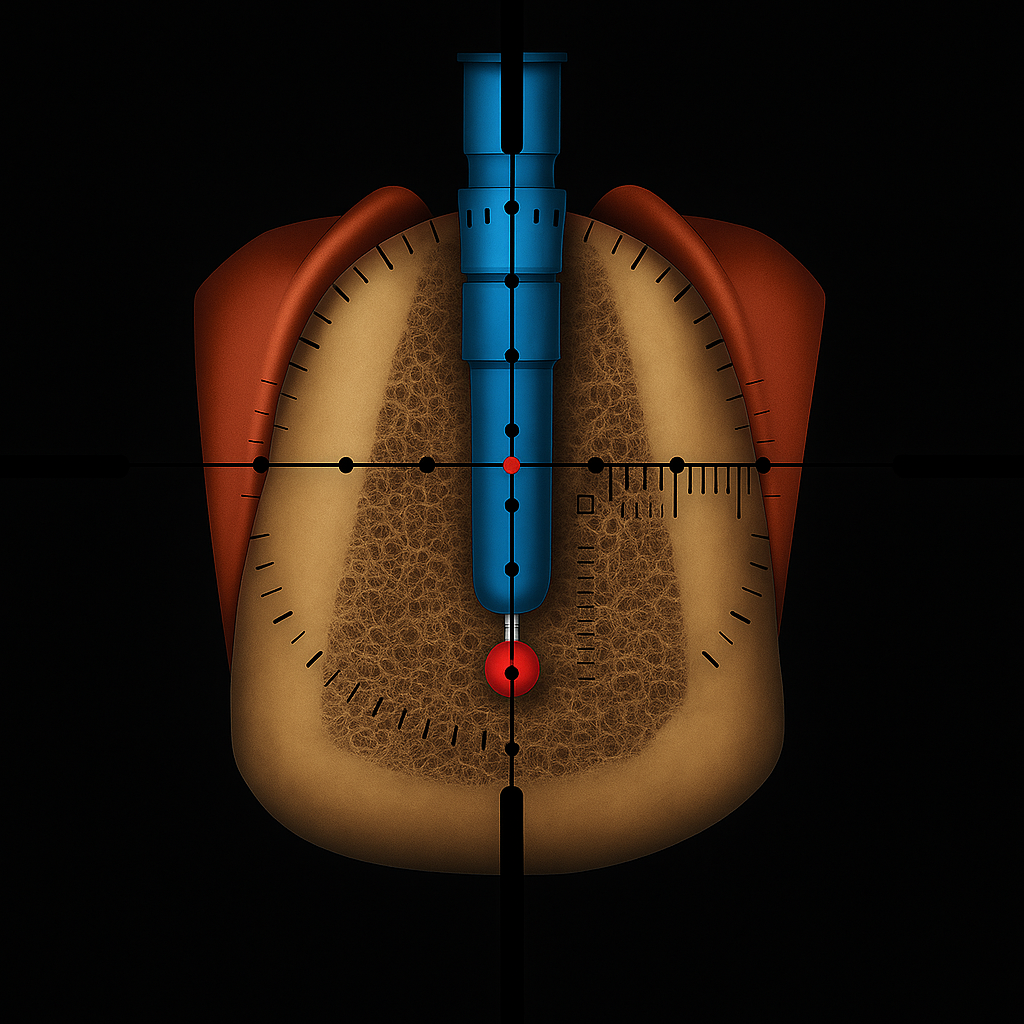

It is desirable to have a method of checking during the surgical procedure that allows to verify if the position, direction and the length of the drill are correct.

By fitting Sniper Xray to conventional film holder allows for consistent orthogonal radiographs and greater measurement precision.

Preliminary testing conducted by oral and maxillofacial radiologists at the University of Texas – San Antonio demonstrated Sniper Xray’s ability to maintain consistent projection geometry and deliver high precision in intraoperative periapical imaging.